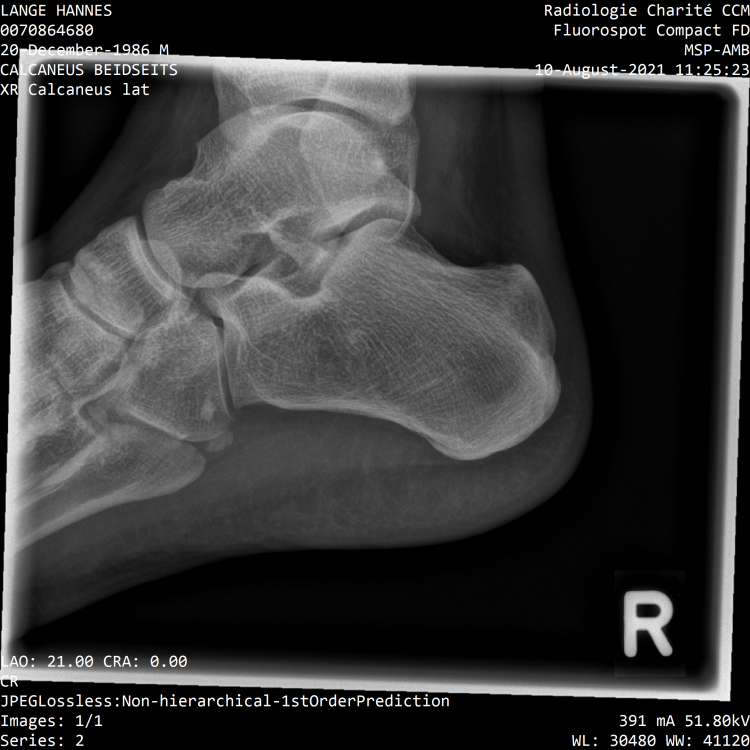

Meine nochmal zum Vergleich Wie war das noch, wurde bei dir hinten operiert und der Knochen abgetragen? Ich habe ja diese Haifischflosse.- 161 Antworten

Stimmt in deinem MRT kann man auch die dorsalen Sporne erkennen. Das zeigt ja eindeutig das bei dir auch die rückseitige Kette verkürzt ist und sie gedehnt werden muss. Die plantaren Sporne sind dann wohl noch nicht verknöchert, dann würde ich hier auch viel die plantare Sehne dehnen und jeden Tag mehrmals den Fuß auf Golfball und Flummies ausrollen, vorallem auch im Bereich der noch nicht verknöcherten Sporne, so kannst du den Prozess der Verknöcherung vielleicht aufhalten. Ich glaube der Körper versucht mit den Spornen der verkürzen Sehne entgegenzukommen. Je kürzer die Sehne desto länger muss der Sporn sein. Je höher die Zugkräfte des schneller entstehen die Sporne. kannst du die Röngtenaufnahmen hochladen? Ich dehne mittlerweile 1. vor dem Aufstehen 2. ca. 2-3h später 3. nach der Arbeit ca. 19 / 20Uhr 4. Kurz vor dem ins Bett gehen Das hat sich bisher am effektivsten gezeigt. Evtl. auch nochmal ein zwischen dem 3. und 4. mal dehnen. Die ersten beiden Dehnungen sind meiner Meinung nach die Wichtigsten da mit der 1. die Verkürzung aus der Nacht reduziert wird und mit der 2. kommt man wieder auf den Zustand vom Vortag. Die ersten beiden male dehne ich auf zwei verschiedene Varianten. Einmal mit dem Spanngurt über dem Ballen für eine gute Dehnung von Wade und Oberschenkel und dann den Spanngurt über die Ferse für eine gute Dehnung des Oberschenkels. Bei mir geht es immernoch nur sehr langsam voran. Es schwankt auch stark. Ich bin mal optimistisch und sage das ich es dieses Jahr zumindest soweit habe das ich normal meinen Alltag bestreiten kann. Am Montag probiere ich mal die Lasertherapie. Ich glaube aber nicht an einen durchschlagenden Erfolg.- 161 Antworten